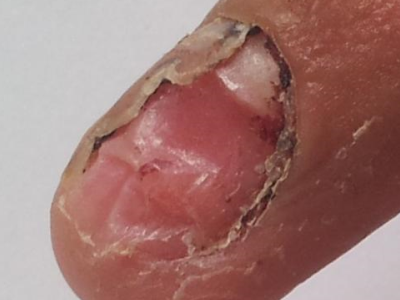

甲床炎症状图片

甲床炎患者受到外伤及细菌感染,可使甲床化脓及发炎,以后甲可以扭曲甚至脱落,严重患者的指(趾)头可以溃烂坏死。天疱疮、疱疹样皮炎、剥脱性皮炎、毛发红糠疹、银屑病、梅毒以及甲板下的异物都可引起甲床炎。

甲床炎患者多存在外伤史,病变一般会先从某一指甲或趾甲开始。真菌、细菌通过甲小皮侵犯甲床,继而甲床出现肿胀、化脓,且通常会伴有疼痛。